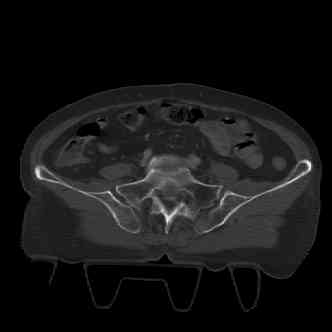

attached are several CT cuts. please let me know if you need more. the CT is pre-pelvic ex-fix placement.

injuries are limited to the pelvis. left rami open and visible in a 10cm vertical laceration just lateral to left labia majora. wound is grossly clean. no vaginal and no urinary issues. CT scan shows widening of both SI joints anteriorly but I think this is vertically stable pattern.

so the question is what next operatively if anything? concerns are infection, nonunion anteriorly and possible incompetence of the pelvic floor which may lead to prolapse issues. right rami are comminuted and plating may entail ilioinguinal approach to extend plate laterally to right iliac wing. retrograde screw up right rami is an option but I am not convinced it will add much. adding SI screws very doable, but major concern is restoring anterior ring. so far wound is clean and closed over a drain, and I have no plans to open it back up and wash again.